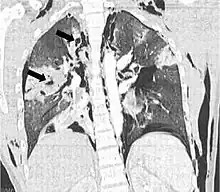

| Coronal CT scan showing lucencies (pale areas in radiography) in the lung caused by pulmonary lacerations on the left of the image (black arrows) | |

Pulmonary laceration may not be visible using chest X-ray because an associated pulmonary contusion or hemorrhage may mask it.[1][9] As the lung contusion clears (usually within two to four days), lacerations begin to become visible on chest X-ray.[3] CT scanning is more sensitive and better at detecting pulmonary laceration than X-rays are,[1][5][12][15] and often reveals multiple lacerations in cases where chest X-ray showed only a contusion.[12] Before CT scanning was widely available, pulmonary laceration was considered unusual because it was not common to find with X-ray alone.[12] On a CT scan, pulmonary lacerations show up in a contused area of the lung,[9] typically appearing as cavities filled with air or fluid[16] that usually have a round or ovoid shape due to the lung's elasticity.[4]